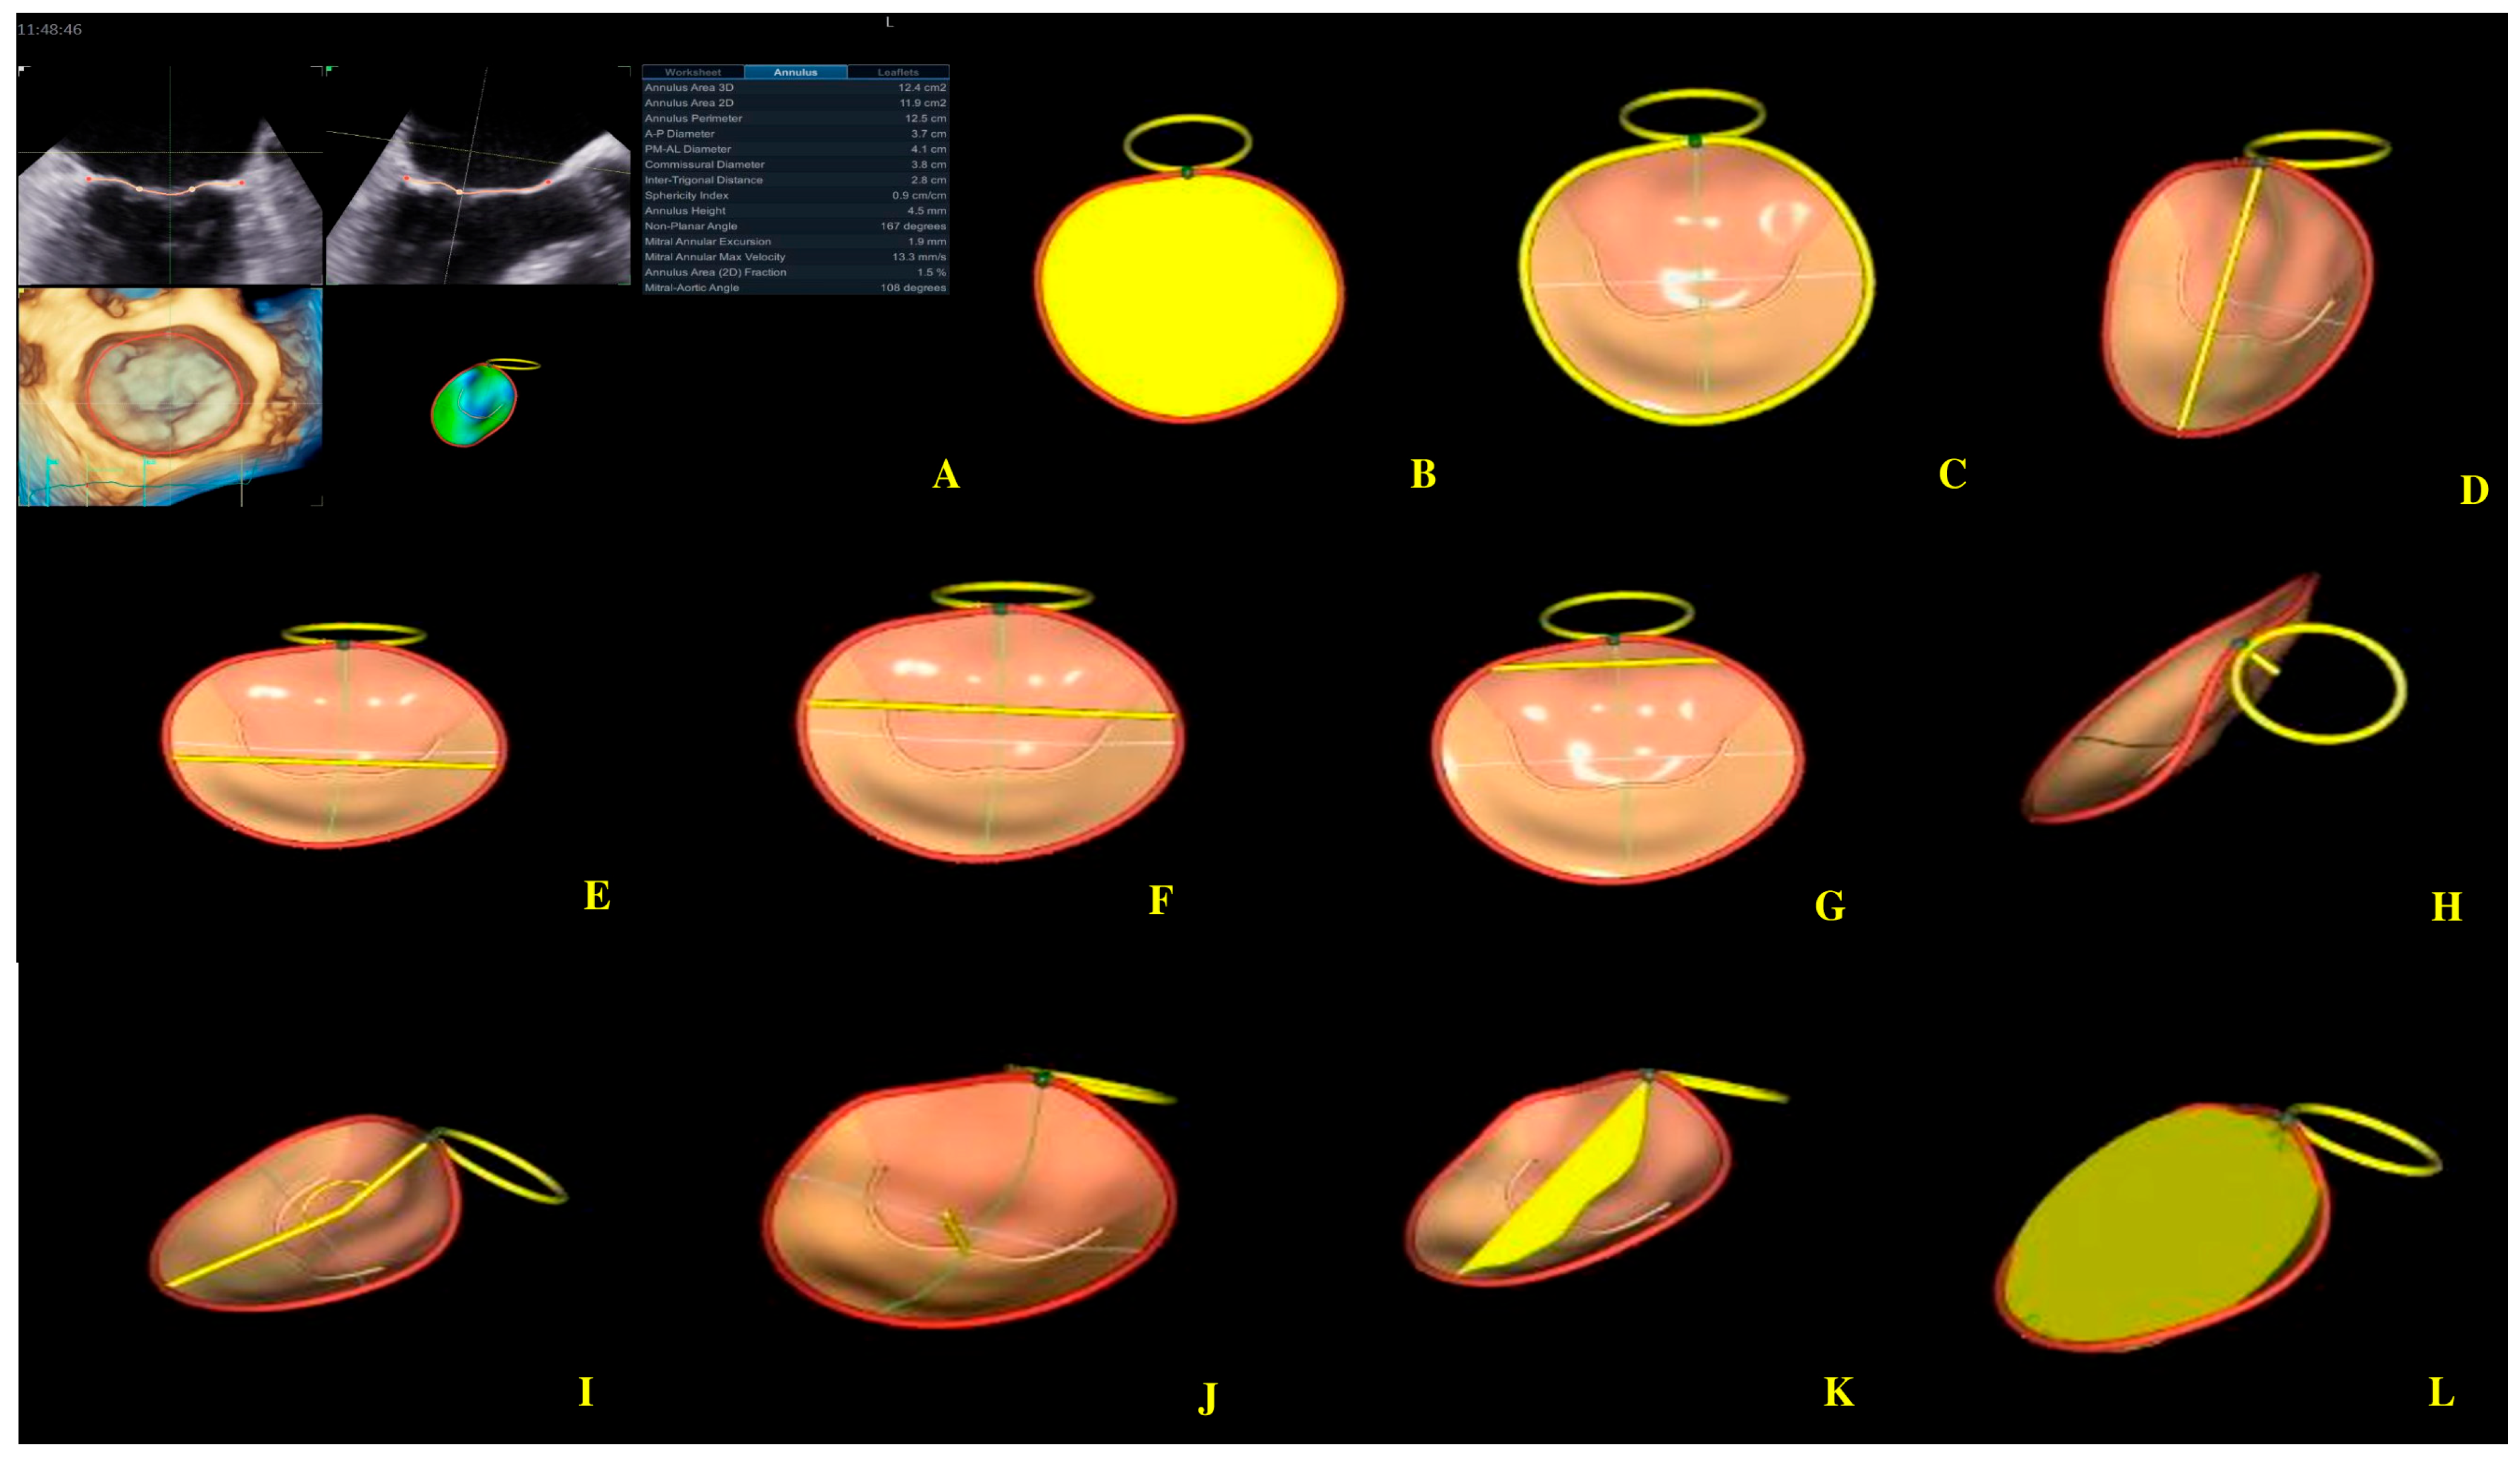

Figure 5.

Mitral annulus parameters provided by Four-Dimensional Auto Mitral Valve Quantification (4D Auto MVQ) software: (A) Final parameters values; (B) AA—annular area; (C) AP—annular perimeter; (D) AP diameter—anteroposterior diameter; (E) PM-AL diameter—posteromedial to anterolateral diameter; (F) CD—commissural distance; (G) Itd—intertrigonal distance; (H) AH—annular height; (I) NPA—nonplanar angle; (J) TH—tenting heigh; (K) TA—tenting area; (L) TV—tenting volume.

In healthy humans, the MA is essential for the structural and functional integrity of the MV complex, reducing stress exerted by LV forces on the mitral valve leaflets [32,37]. During the LV contraction, the MA folds from early to mid-systole and increases its saddle-shape configuration. During late systole to diastole, the MA gradually expands back [38]. Four-dimensional echocardiography has significantly enhanced the understanding of the anatomy of the mitral valve apparatus [39,40,41]. RT4DE is a useful imaging technique for identifying differences in MA shape and function in cardiac diseases [8]. MA morphological parameters provided by RT4DE are AA, AP, APd, PM-ALd, CD, ITD, AH, NPA, and MAA [38,42] (Figure 5).